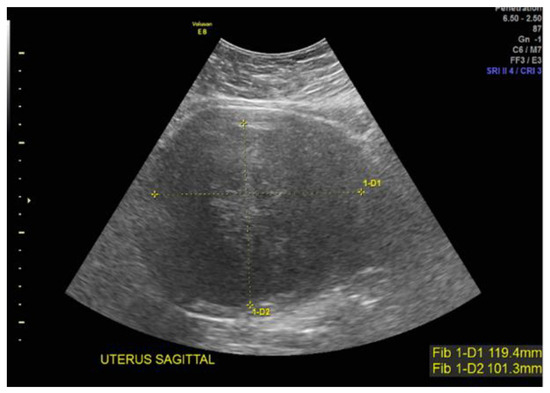

Case 1: A 37-year-old White, non-Hispanic patient presented with heavy menstrual bleeding and pelvic pain. A pelvic ultrasound revealed a 4.5 cm intramural uterine fibroid (Figure 1A) and a 3.5 cm submucosal uterine fibroid (Figure 1B). She underwent a total laparoscopic hysterectomy with bilateral salpingectomy. Pathology confirmed a leiomyoma with features of FH deficiency; germline genetic testing was negative for known pathogenic mutations.

Figure 1. (A) Anterior intramural uterine fibroid. (B) Anterior submucous uterine fibroid.